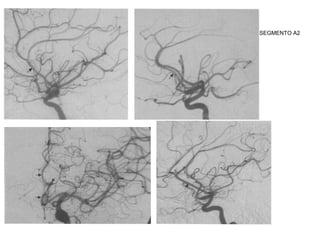

SEGMENTO A2

• A2 (infracaloso): começa na AcomA, dirige à lamina

terminal e termina na junção do rostro do corpo caloso.

As setas indicam M2 contornando o

sulco circular da ínsula. A seta maior o

ponto silviano posterior, emergência da

artéria angular.